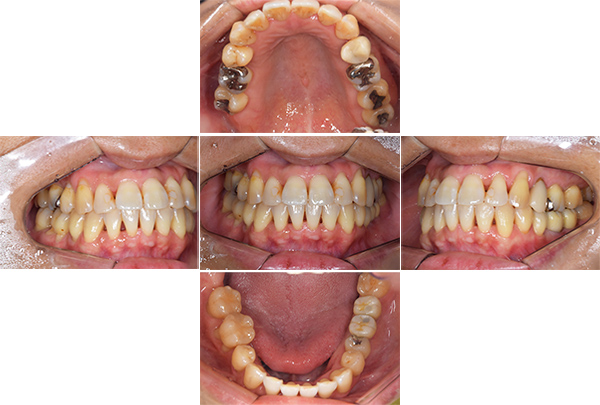

症例写真(治療後)

治療後:

矯正治療と虫歯の治療すべて終わったときの写真になります。見た目も最初の頃とは全く違いますし、お口の中もすごく綺麗です。